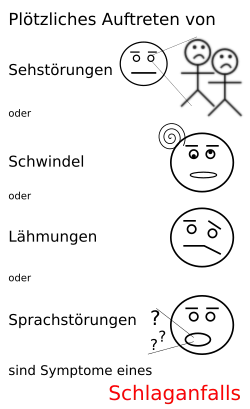

Symptome

Beim ischämischen Schlaganfall kommt es typischerweise zu einem plötzlichen Auftreten mehrerer Symptome. Die Symptomatik kann auch fluktuieren oder allmählich zunehmen. Die Symptomatik erlaubt aber keine Differenzierung der Ursachen eines Schlaganfalls.

- Bewusstseinstrübung: Diese kann von einer leichten Benommenheit über Müdigkeit (Somnolenz, Sopor) bis hin zur Bewusstlosigkeit oder zum tiefen Koma reichen. Schlimmstenfalls kann ein Schlaganfall auch innerhalb von Minuten zum Tod durch Atemstillstand führen. Die Bewusstseinsstörung gehört zu den Leitsymptomen bei Infarkten im hinteren (vertebrobasilären) Stromgebiet.

- Halbseitenlähmung (Hemiparese) oder Lähmung einer Gliedmaße (nur selten Lähmung aller Extremitäten)